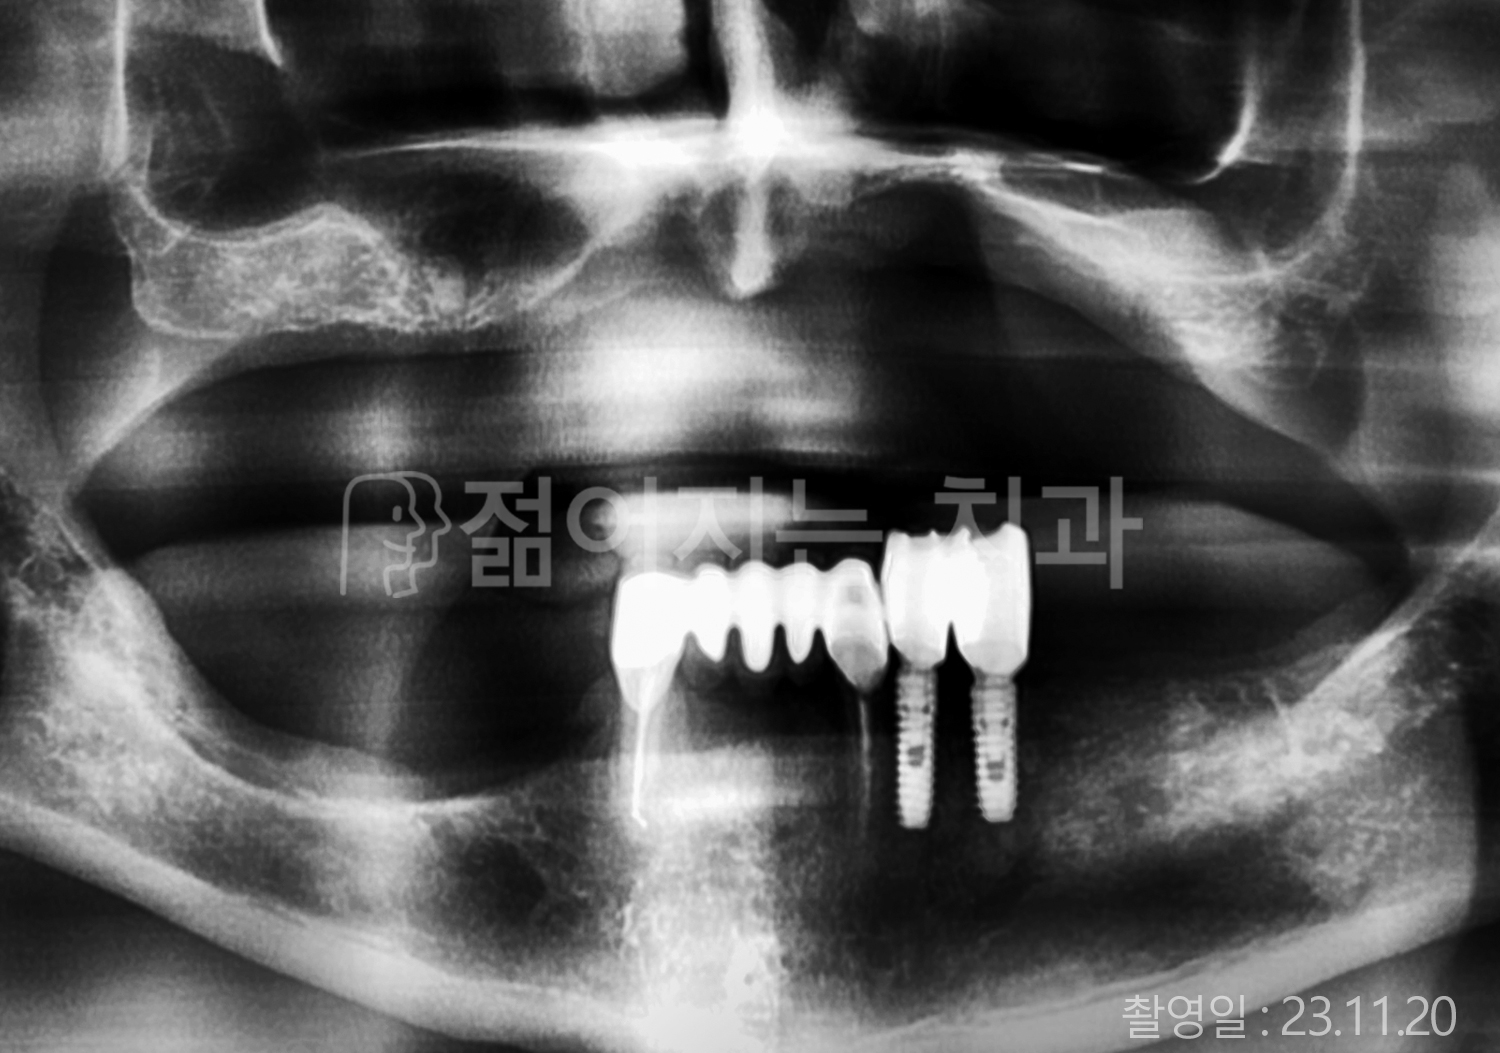

• 80대 전체치아 10개 이상 임플란트

• 60대 고혈압, 당뇨, 고지혈증 전체치아 10개 이상 임플란트

• 60대 전체치아 10개 이상 임플란트

• 60대 고혈압, 고지혈증 전체치아 10개 이상 임플란트

• 50대 고혈압, 당뇨, 고지혈증 전체치아 10개 이상 임플란트

• 70대 골다골증, 파킨스병 전체치아 10개 이상 임플란트

• 40대 전체치아 10개 이상 임플란트

• 60대 골다골증 전체치아 10개 이상 임플란트

• 40대 고혈압 전체치아 10개 이상 임플란트

• 50대 전체치아 10개 이상 임플란트

• 70대 전체치아 10개 이상 임플란트